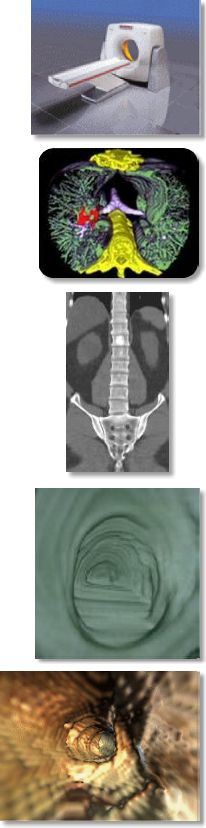

- Virtual colonoscopy, bronchoscopy, and endovascular angioscopy

AIC has been offering for some time a screening program called ScanHealth, which includes a screening helical CT of the torso, CT coronary calcium scoring, and more optional 4D virtual colonoscopy (images on the right). Please kindly inform your patients that this program is now offered in their own backyard so they no longer have to travel hundreds of miles to get this test.For more information, please call me personally at (661) 949-8111 and/or visit our website at www.aicLancaster.com.